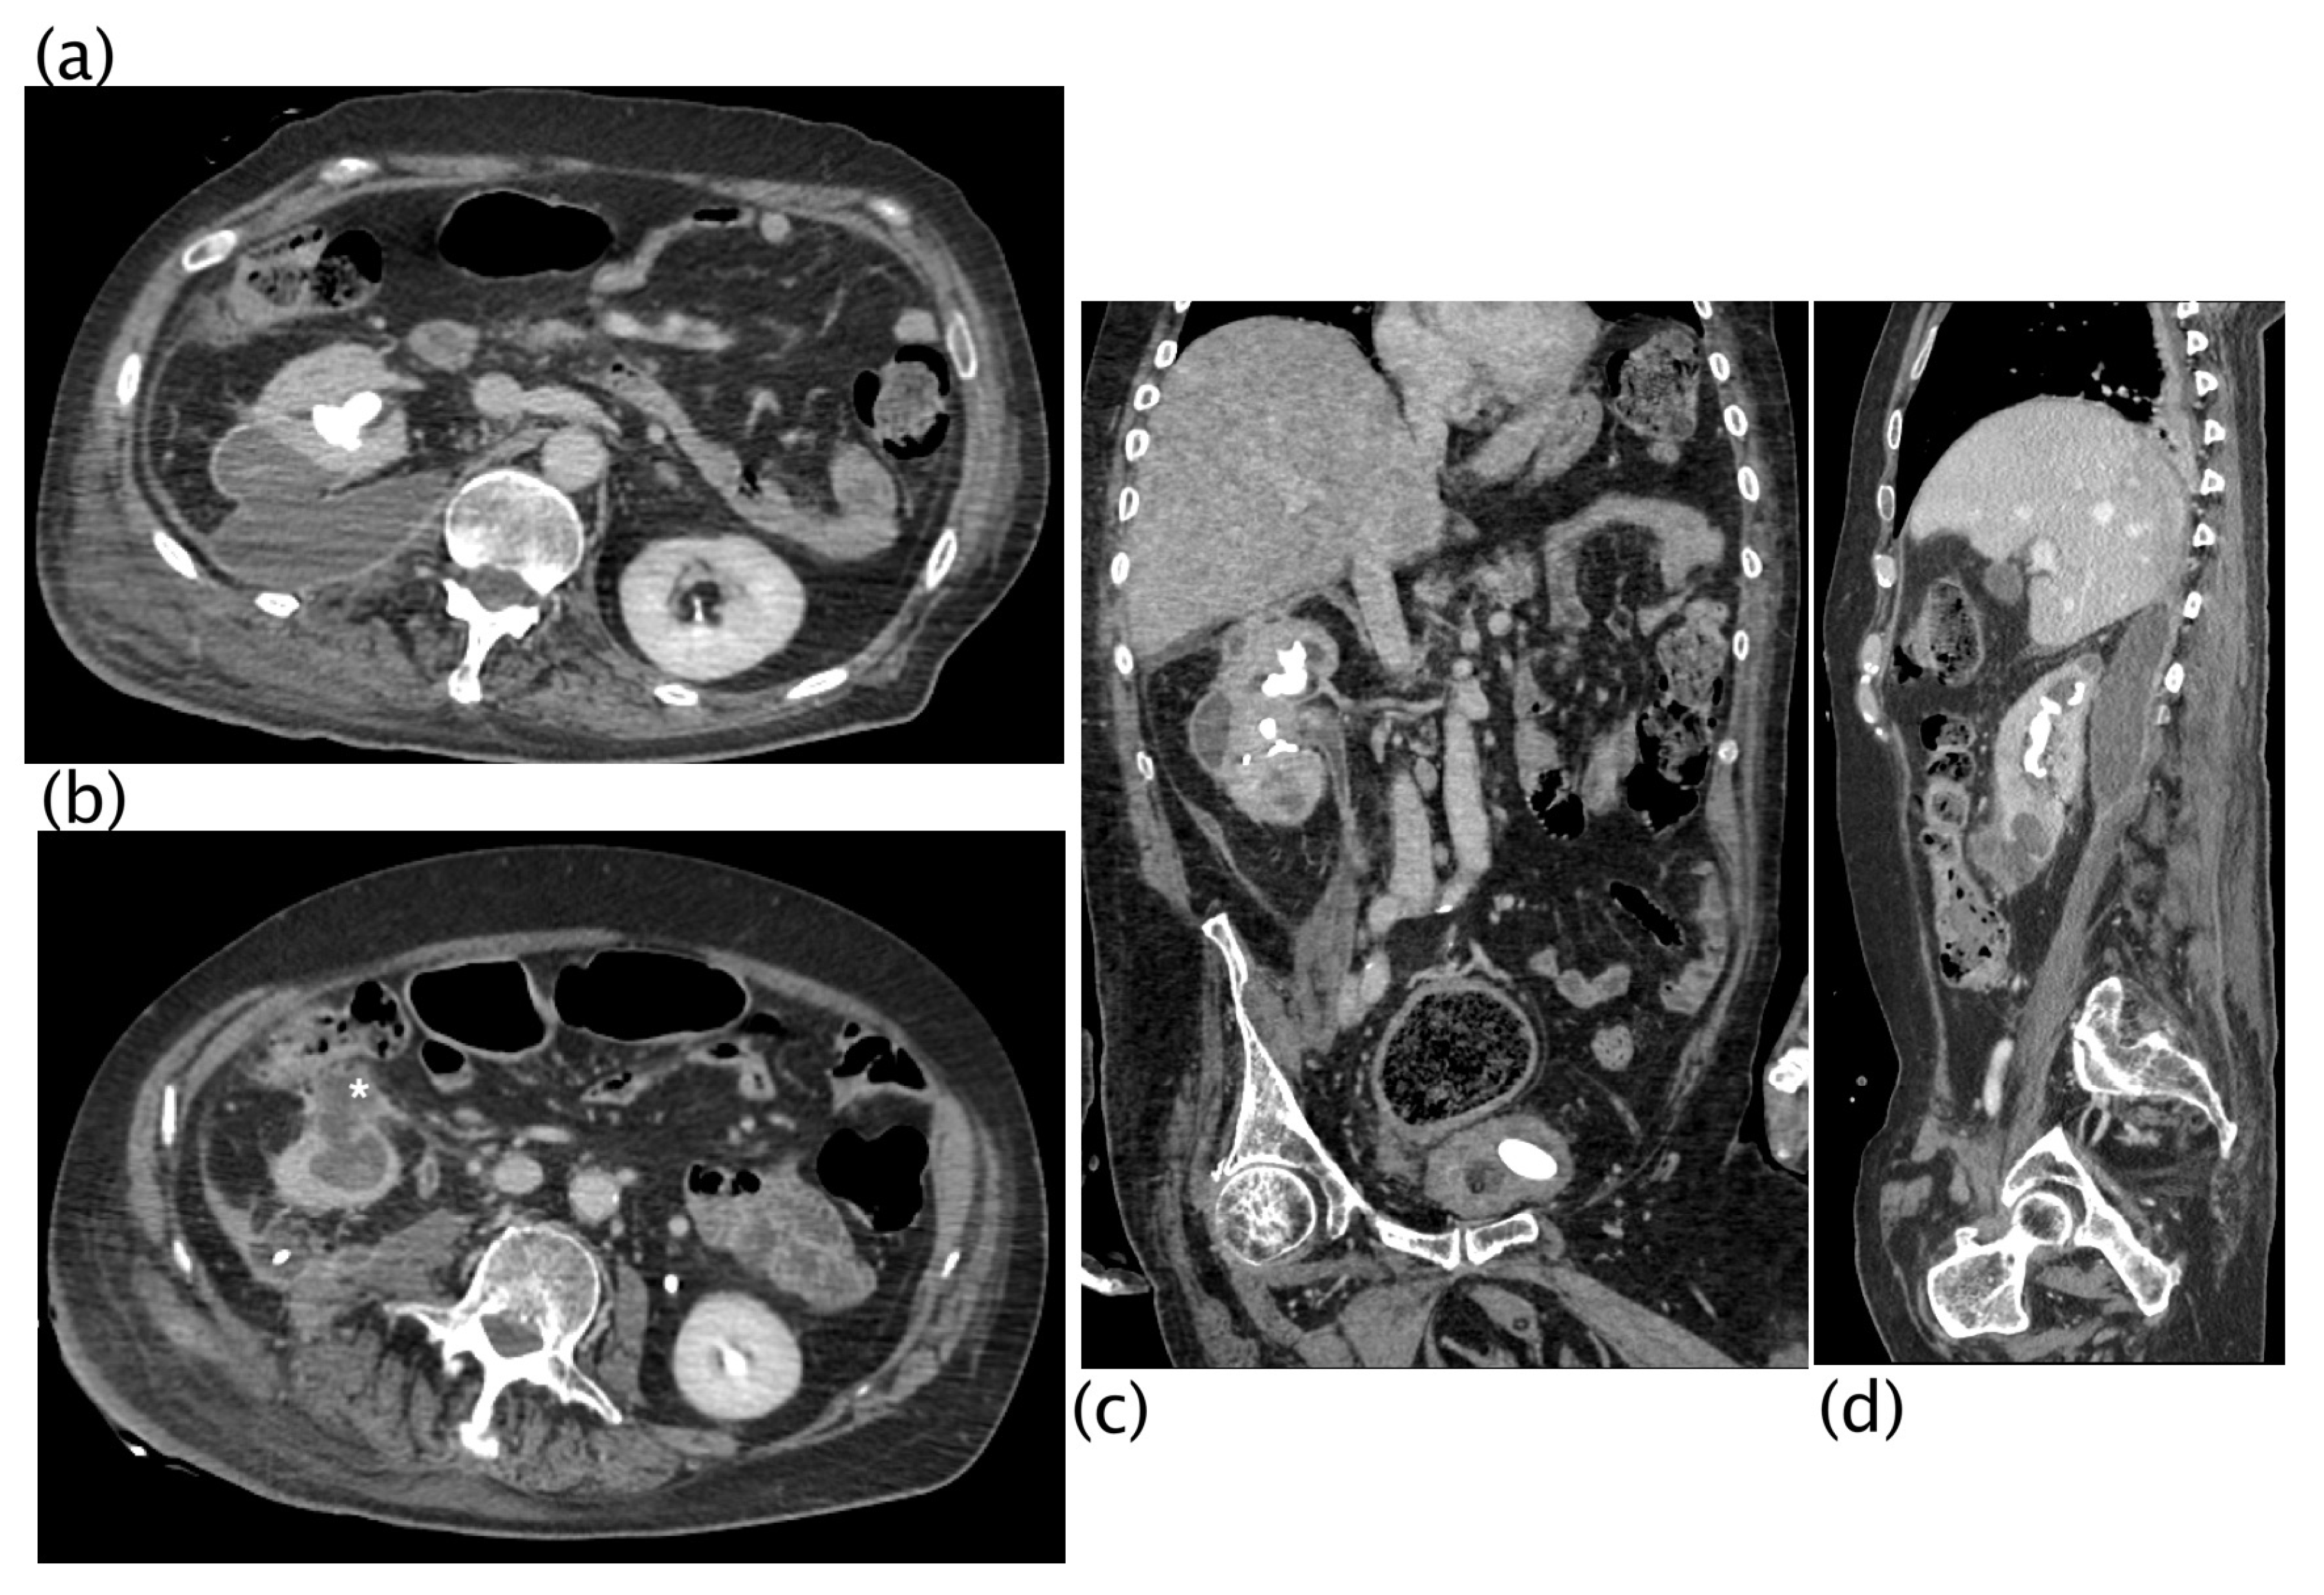

Figure 5.

Xanthogranulomatous pyelonephritis Stage III—pararenal form CT with contrast agent: axial (a,b), coronal (c), and sagittal (d) MPR reconstruction. In the right kidney, staghorn lithiasis is present; gross vesical lithiasis is also visible. The walls of the ureter are thickened and hyperemic. The CT was performed after nephrostomy placement, so significant calico-pyelic dilatation is not significant. Peri- and pararenal collections are evident, particularly the inferior polar collection (c) that passes the perirenal fascia. Posteriorly (b), the inflammatory process passes and infiltrates the psoas muscle. The staghorn lithiasis, the coexistence of calico-pyelic dilatation and fluid collections, and especially, the high invasiveness of the pathology, allowed, with high diagnostic confidence, to make the diagnosis of XGP.